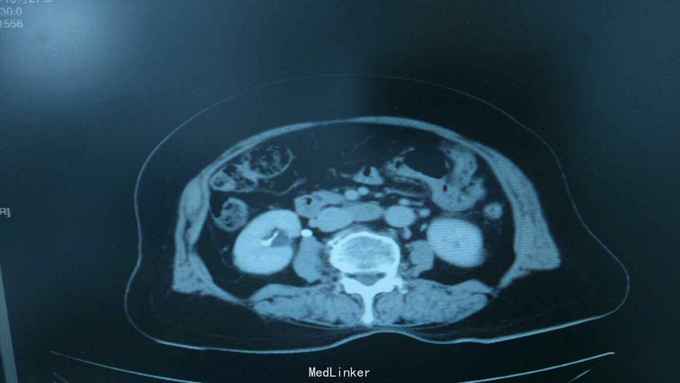

68岁,女性。 主诉:左侧腰痛1年,加重1个月。 病史:1年前无明显诱因出现左侧腰痛,无恶心呕吐,无肉眼血尿。1个月前加重,于外院查泌尿系彩超显示:左肾积液,输尿管显示不清。

诊断:双肾盂旁囊肿 治疗:因患者肾盂未明显受压,疼痛症状不明显,等待观察,暂未予处理。

双侧同时出现的病例并不多见,临床只能通过泌尿系统CTU或增强CT加以鉴别,彩超无法区分肾盂积水及盂旁囊肿。